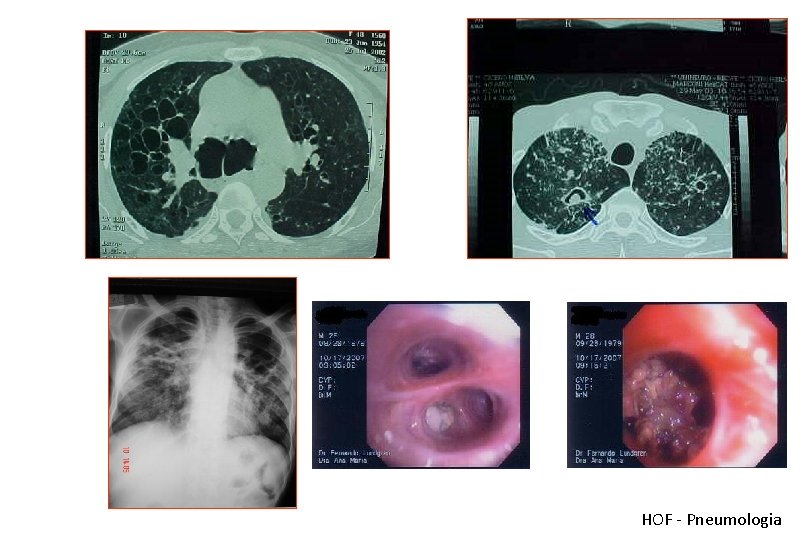

Bronquiectasias Quadro Clínico Tosse Produtiva Secreção Abundante Hemoptise Repetição Sépsis crônica Caquexia Diária Odor Alteração do humor O’Donnel AEBA at al. Chest 1998; 113(5): 1329 -34

Bronquiectasias

HOF - Pneumologia